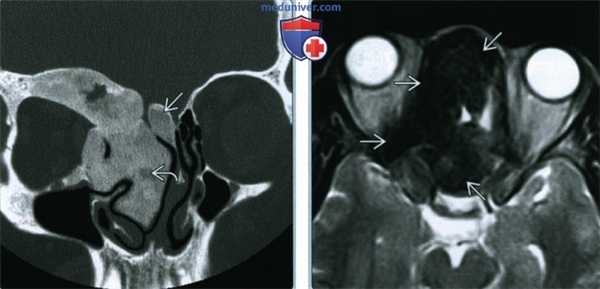

(Слева) На корональной КТ в костном окне определяется ПФД с поражением глазницы, петушиного гребня, решетчатого лабиринта, средней носовой раковины справа. Оцените типичную картину «матового стекла». Носовая перегородка смещена влево.

(Справа) На аксиальной МРТ (Т2ВИ) у этого же пациента определяется выраженный гипоинтенсивный сигнал в пораженных костях. Поражение однородное и сопоставимо с «матовым стеклом» на КТ. При большем количестве фиброзной ткани ожидаемы очаги с более интенсивным сигналом и более длительным временем повторения.